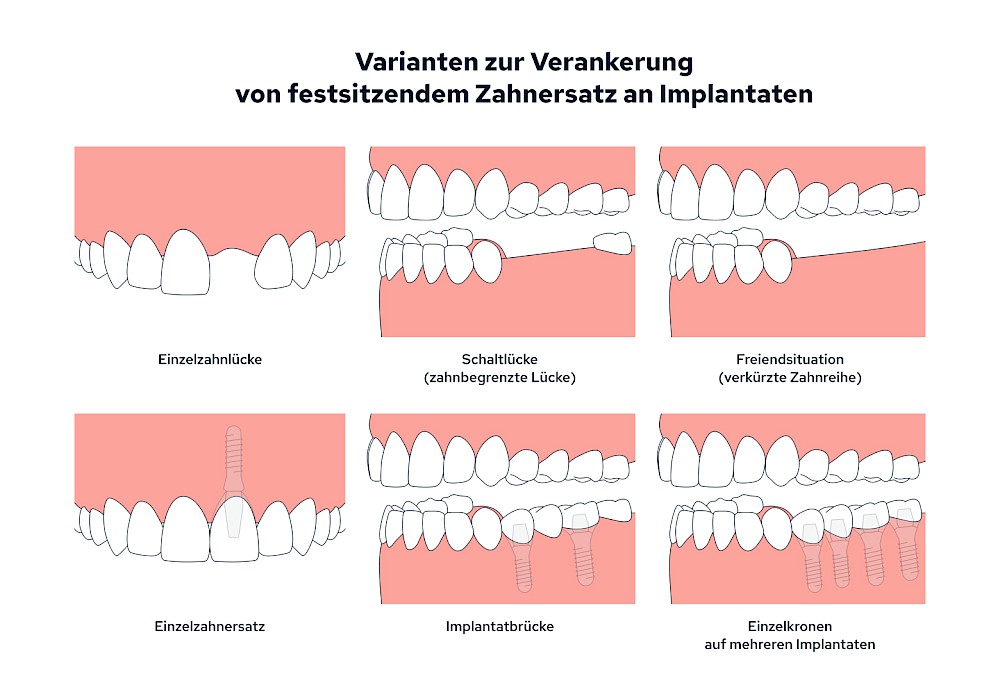

Fehlen einzelne Zähne und die Nachbarzähne sind unbeschadet oder gut zahnärztlich versorgt, werden immer häufiger Implantate gewählt um die Lücken zu schließen. Auch bei größeren oder verteilten Lücken, wenn keine herausnehmbare Prothese gewünscht ist, werden Implantate für Kronen- bzw. Brückenversorgungen gesetzt. In Einzelfällen entscheiden sich sogar zahnlose Patienten für eine festsitzende Versorgung auf Implantaten.

Bei herausnehmbaren Prothesen werden Implantate eingesetzt, um den Halt und den Tragekomfort der Prothesen zu verbessern. Dazu kommen verschiedene Verbindungselemente zum Einsatz: